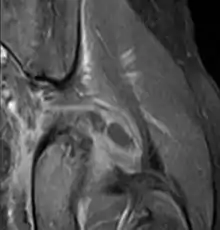

يعتمد تشخيص التهاب العضلات التقيحي على الفحص الاكلينيكي والتاريخ المرضي للمريض. ويظل التصوير بالرنين المغناطسي هو الفحص الأكثر دقةَ لتحديد الإصابة بهذا المرض.[3]